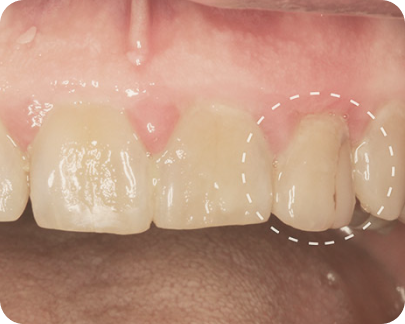

Пациент обратился с жалобой на боль при накусывании на передний зуб.